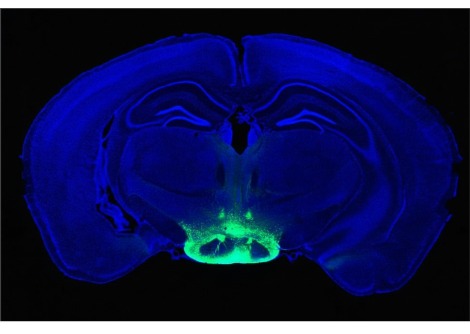

أظهر بحث جديد أن الهواء الذي ينفخ من مروحة كهربائية وحده لا يكفي لتبريد كبار السن الذين يعانون من الحر الشديد في الداخل. وجدت دراسة أجريت على 18 بالغًا تتراوح أعمارهم بين 65 و72 عامًا، تم رصدهم في غرفة مناخية خاضعة للرقابة تحاكي ظروف موجة الحر الشديدة، اختلافًا ضئيلًا في درجات الحرارة الأساسية القصوى نتيجة لاستخدام المروحة الكهربائية، وفقًا لتقرير العلماء في 17 أكتوبر في مجلة الجمعية الطبية الأمريكية.

لذلك قرر عالم وظائف الأعضاء البيئية فيرجوس أوكونور، الذي يعمل الآن في جامعة جريفيث في بريسبان بأستراليا، وزملاؤه اختبار قوة تبريد المراوح بشكل مباشر أثناء ظروف موجة الحر. أمضى المشاركون في الدراسة ثلاث حلقات مدة كل منها ثماني ساعات جالسين في غرفة بجامعة أوتاوا، مع ضبط درجة الحرارة على 36 درجة مئوية (96.8 درجة فهرنهايت) ورطوبة نسبية 45 في المائة. هذه الظروف تشبه المناخ الذي تحمله مواطنو فانكوفر خلال موجة الحرارة التي استمرت أسبوعًا والتي استقرت فوق كولومبيا البريطانية في عام 2021، مما أدى إلى وفاة ما يقدر بنحو 619 شخصًا في المقاطعة .

كما تحتوي الغرفة التي يتم التحكم في مناخها على مروحة كهربائية. افترضت النماذج السابقة التي تحاكي فعالية المروحة تدفق هواء قوي جدًا يبلغ حوالي 3.5 إلى 4.5 متر في الثانية. لكن الباحثين لاحظوا أن هذه قوة أكبر مما تستطيع العديد من مراوح المنازل القياسية تقديمه. لذا فإن كل فترة تعرض تضمنت سرعة مختلفة للمروحة ، لا يوجد تدفق هواء، وتدفق هواء بطيء يبلغ 2 متر في الثانية وتدفق هواء سريع يبلغ 4 أمتار في الثانية.

قام الفريق بتقييم درجة حرارة الجسم الأساسية للمشاركين، والإجهاد القلبي الوعائي، ومستوى الجفاف، والراحة الحرارية - وهي الشعور بالحر أو البرد الشديد. وأشارت النتائج إلى أنه مقارنة بحالة التحكم بدون تدفق هواء على الإطلاق، فإن تدفق الهواء الأبطأ لم يؤدي إلى تغييرات كبيرة في درجة حرارة الجسم الأساسية، أو ضغط الدم، أو استهلاك السوائل، أو الراحة الحرارية. أدى تدفق الهواء الأسرع إلى تحسين تصورات الراحة الحرارية - ولكن، من الناحية الفيزيائية الحيوية، لم يكن هناك تحسن كبير.